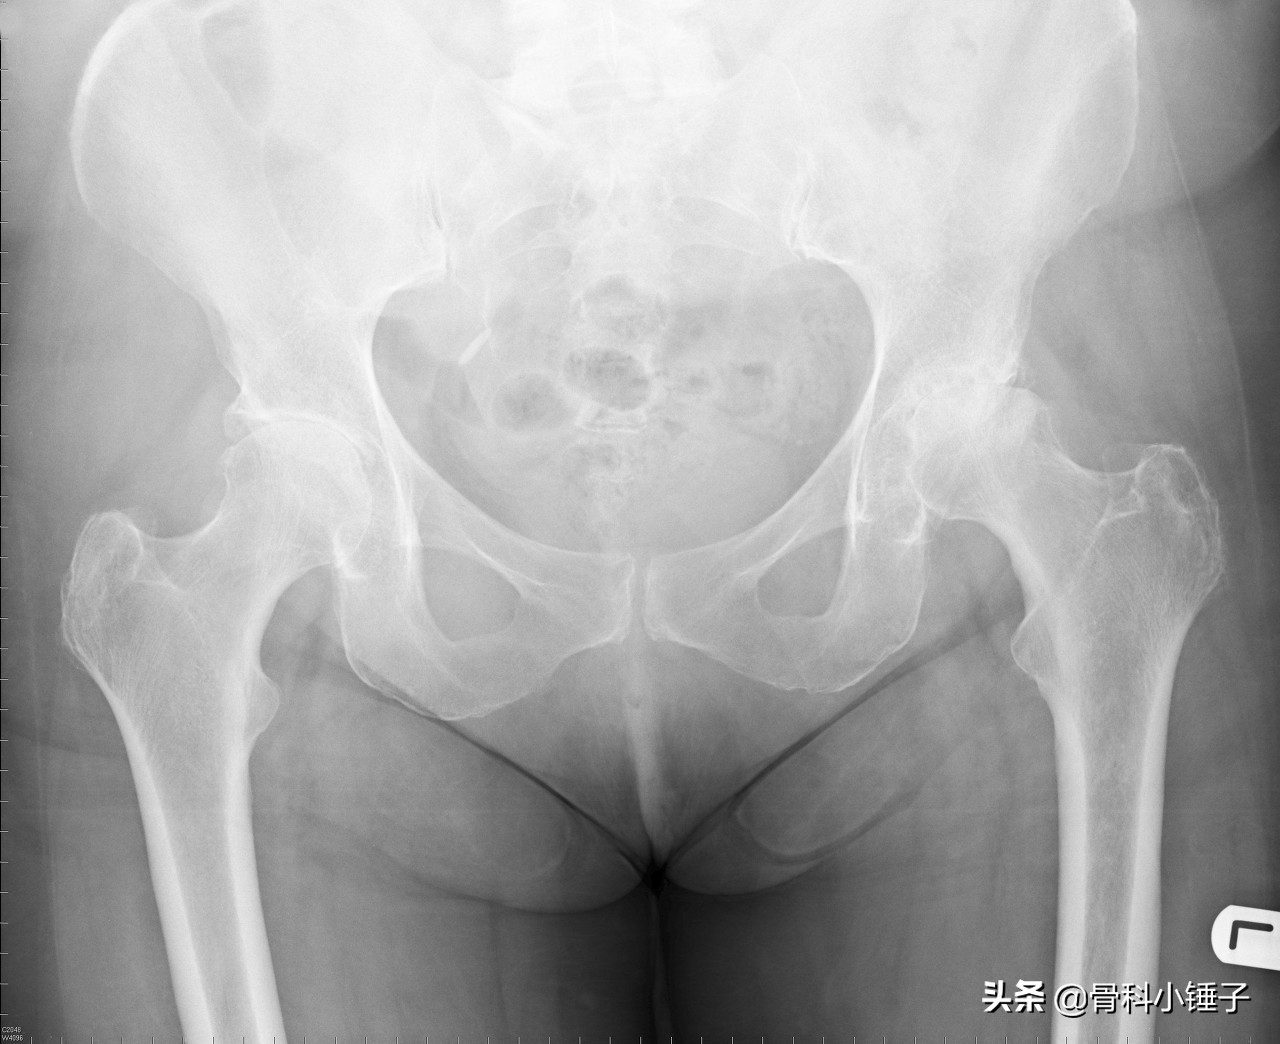

通过X线可以清晰观察到软骨的退化。正常关节面之间的骨结构和间隙状软骨清晰可见。软骨一旦病变,磨损进展很快。当您走路时,关节面之间便不再可能进行无摩擦的运动。